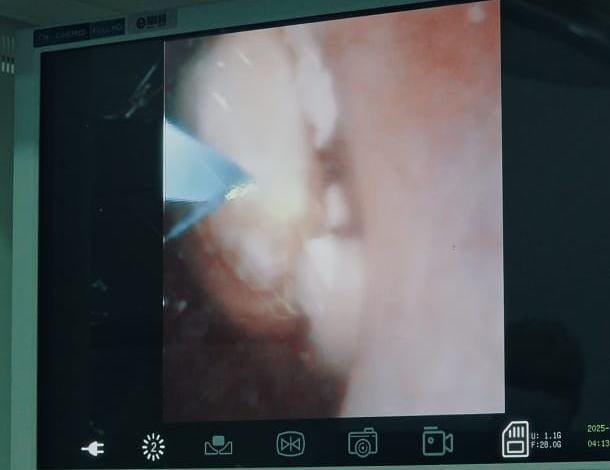

A Santa Casa de Marília passou a disponibilizar recentemente um aparelho de laser de alta potência para tratamentos de cálculos renais. A litotripsia a laser de 30 W é um dos padrões mais usados em centros urológicos. Ela combina boa potência, controle e versatilidade, permitindo tratar praticamente qualquer cálculo urinário com segurança.

O procedimento garante alta eficiência e versatilidade, fragmenta qualquer tipo de cálculo (oxalato, cistina, ácido úrico, brushite, etc.), independentemente da dureza, é útil tanto para ureteroscopia rígida quanto flexível e indicado para cálculos renais, ureterais e vesicais.

“É o equilíbrio ideal entre potência e controle, permitindo combinar energia e frequência com excelente controle térmico. O equipamento oferece baixo risco de dano tecidual, atuando por absorção em água, com profundidade de penetração de apenas 0,4 mm, segurança elevada para mucosa ureteral e pielocalicial, além de ter menor chance de perfuração ou necrose comparado a métodos mecânicos ou ultrassônicos”, salientou Guzzardi.

O aparelho de laser adquirido pela Santa Casa de Marília também oferece maior controle intraoperatório, possibilitando tratamento completo em uma única sessão.